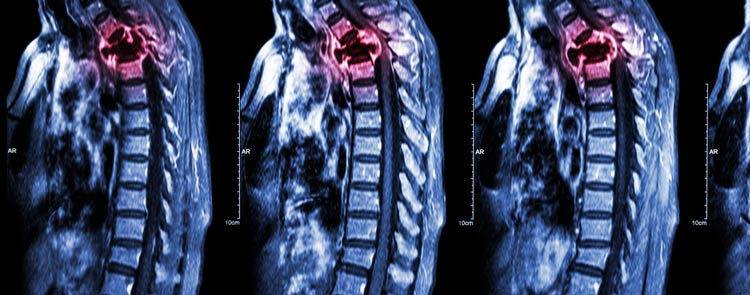

- Чаще всего вторичные отсевы рака возникают в обильно питаемых кровью губчатых костях — позвонках, причём преимущественно в испытывающих высокую нагрузку поясничных и грудных отделах позвоночника.

- синдром сдавления или компрессии спинного мозга осколками сломанного грудного или поясничного позвонка осложняется тяжелыми неврологическими нарушениями ниже зоны повреждения;

- нарушение двигательной активности вплоть до паралича возможно при сдавлении спинного мозга в шейном отделе остеобластическим очагом или повреждении отломками при литическом разрушении.

Дополнение химиотерапии локальным облучением позволяет повысить общий результат терапии, снять боль и уменьшить вероятность перелома. Так при поражении шейных позвонков лучевая терапия обязательна уже на первом этапе.